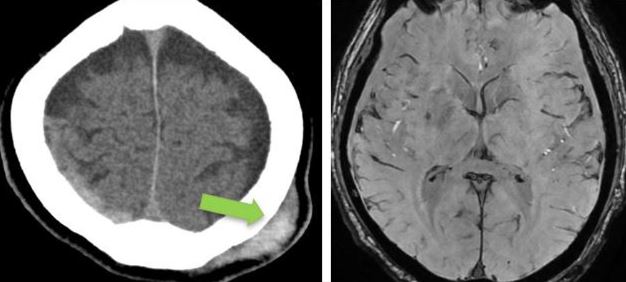

- CT brain – 11 June. Day 2 post mild head injury (after second fall).

Bilateral fronto- parietal hypodense subdural hemorrhage / effusion widest at frontal region, right measures 10 mm keft measures 13 mm in thickness.

There is hyperdense component seen at right parietal region (9 mm in thickness). Mild enhancement of the sulci bilaterally.

Gray-white matter differentiation fairly preserved.

No hydrocephalus.

No skull fracture.

Left parietal scalp swelling.

Impression: Bilateral fronto-parietal subdural hemorrhage as described.

- CT brain. Comparison made with CT brain yesterday – 12 June 2024.

Impression: Right parietal extra-axil haemorrhage, stable in size compared to previous.

Bilateral fronto-temporo-parietal subdural hygroma.

No new intracranial haemorrhage.